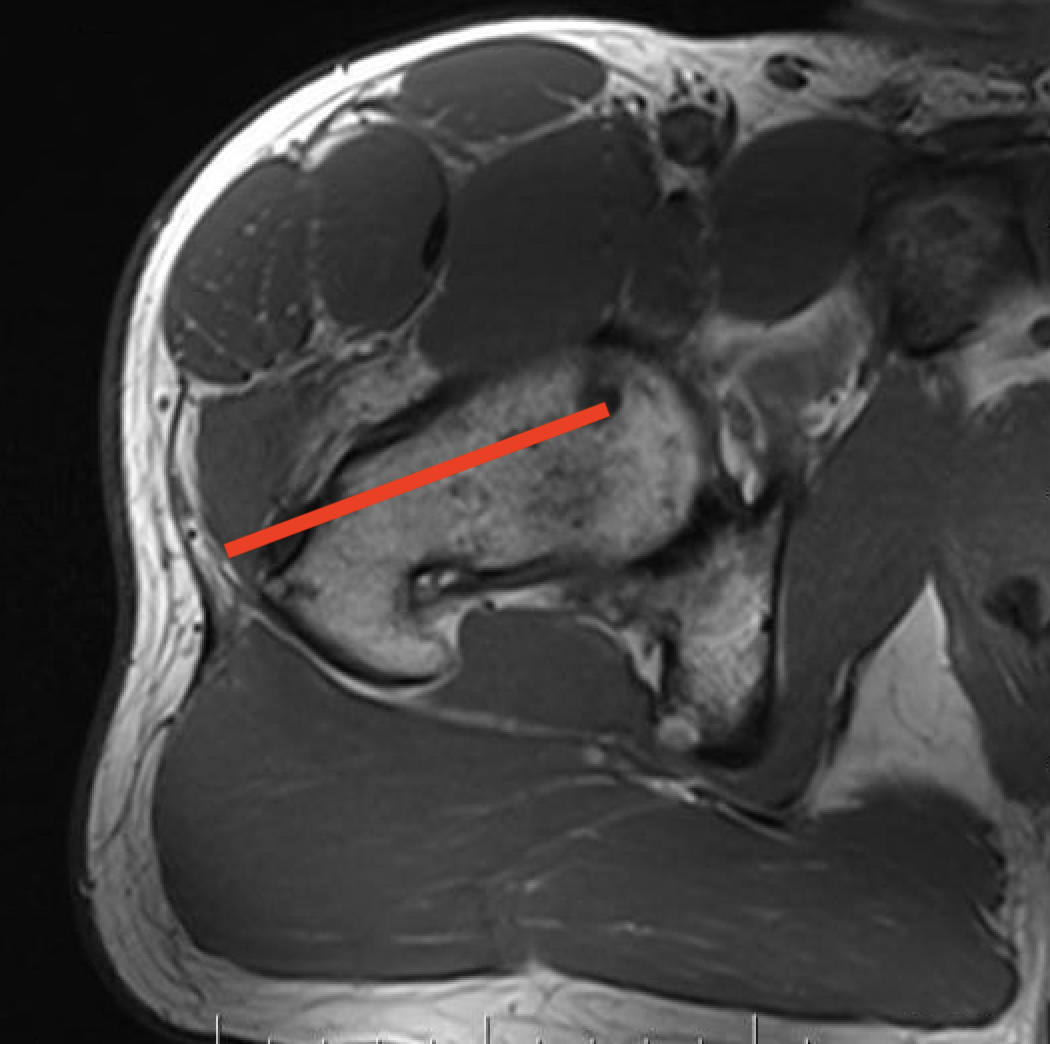

1.  Proximal humeral bony tumour

- direct lateral

- through deltoid muscle

- never deltopectoral (condemns patient to forequarter amputation)

Shoulder CSHumerus biopsy 1